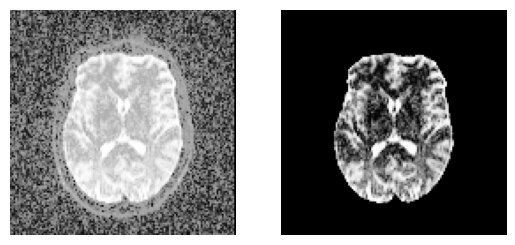

Quick view of the results middle slice using matplotlib.

sli = data.shape[2] // 2

plt.figure("Brain segmentation")

plt.subplot(1, 2, 1).set_axis_off()

plt.imshow(histeq(data[:, :, sli].astype("float")).T, cmap="gray", origin="lower")

plt.subplot(1, 2, 2).set_axis_off()

plt.imshow(histeq(b0_mask[:, :, sli].astype("float")).T, cmap="gray", origin="lower")

plt.savefig(f"{fname}_median_otsu.png", bbox_inches="tight")

An application of median_otsu for brain segmentation.